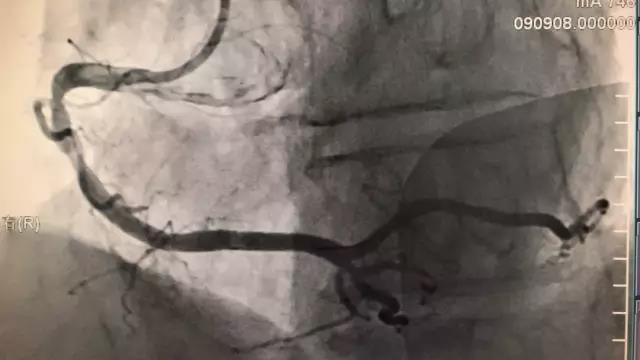

上图,右冠植入一枚支架,原来有病变的血管几乎恢复正常